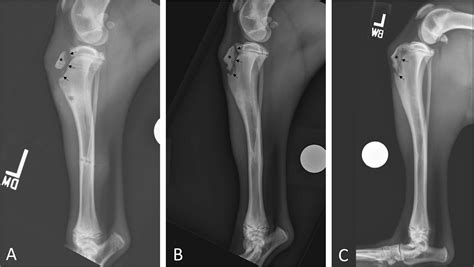

To confirm the diagnosis, medical professionals typically utilize imaging studies. X-rays are the gold standard for visualizing the displaced bone fragment and determining the severity of the fracture. In more complex or comminuted cases, an MRI may be ordered to assess the condition of the surrounding soft tissues, including the patellar tendon and menisci.

Orthopedic surgeons often categorize these injuries based on the Ogden classification system, which helps guide treatment decisions. This classification ranges from simple, non-displaced fractures to complex injuries that extend into the knee joint.

Type Severity Description Typical Treatment

Type I Small fracture at the distal part of the tuberosity. Conservative (casting)

Type II Fracture extends through the secondary ossification center. Surgery often required

Type III Fracture extends into the articular surface of the knee. Surgical intervention

Treatment for a Tibial Tuberosity Avulsion depends heavily on the displacement of the bone fragment. For minor fractures where the bone has not moved significantly, immobilization in a long leg cast or brace for several weeks may be sufficient. During this time, the goal is to allow the bone to heal in its natural position.

However, if the fragment is displaced or if the knee joint is compromised, surgical intervention is mandatory. The surgical procedure typically involves:

• Open Reduction Internal Fixation (ORIF): The surgeon makes an incision to visualize the bone fragment.

• Hardware Placement: The loose piece of bone is secured back to the main tibia using screws, wires, or specialized anchors.